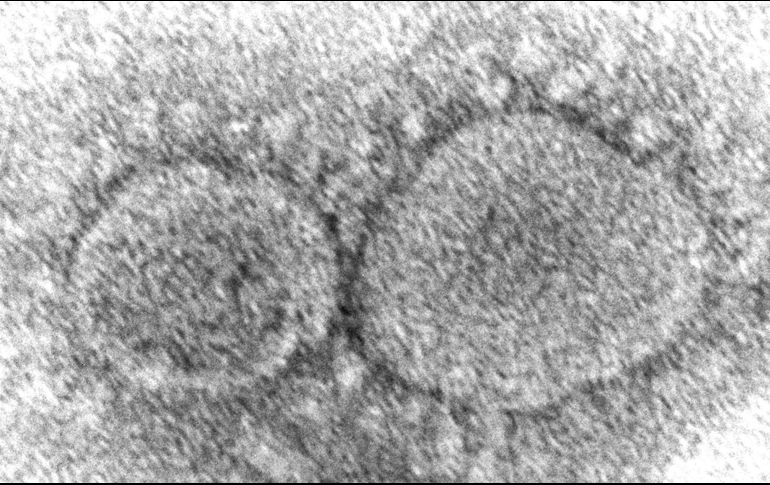

La semana del 26 de noviembre al 2 de diciembre, Florida registró 10 mil 892 nuevos casos de COVID-19. AP/H. Bullock